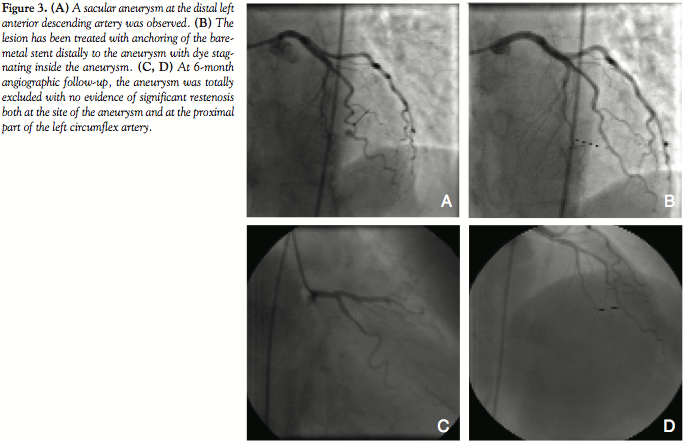

Patient #3. A 56-year-old female with history of hypertention and a mixed connective tissue disease presented with ischemia in the anterior wall (myocardial scintigraphy) and unstable angina. The baseline coronary angiogram revealed a significant stenosis at the proximal LCX artery as well as a sacular aneurysm at the distal LAD artery (Figure 3A). The LAD aneurysm was treated by direct stenting of a 2.5 x 15 mm Tsunami stent (Terumo Corporation, Somerset, New Jersey) at 16 atm which was anchored carefully to the proximal and distal non-diseased segments (Figure 3B). The LCX stenosis was treated with direct implantation of a 3.5 x 13 mm Cypher stent at 14 atm. At 6-month angiographic follow-up, the aneurysm was totally excluded with no evidence of significant restenosis; at 24-month clinical follow-up, the patient was asymptomatic with negative exercise stress tests (Figures 3C and 3D).